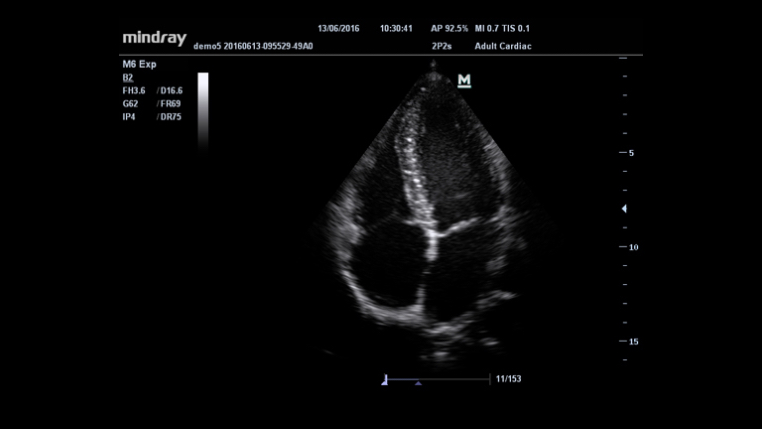

Maximum 8 times tasking for one transmitted beam, resulting in excellent time resolution and higher frame rate.

Gain improved image quality based on auto structure detection.

- Sharper & Continuous Edges

- Smooth Uniform Tissues

- Cleaner ŌĆśno echo areasŌĆÖ

Permits use of multiple scanned angles to form a single image, resulting in enhanced contrast resolution and improved visualization.